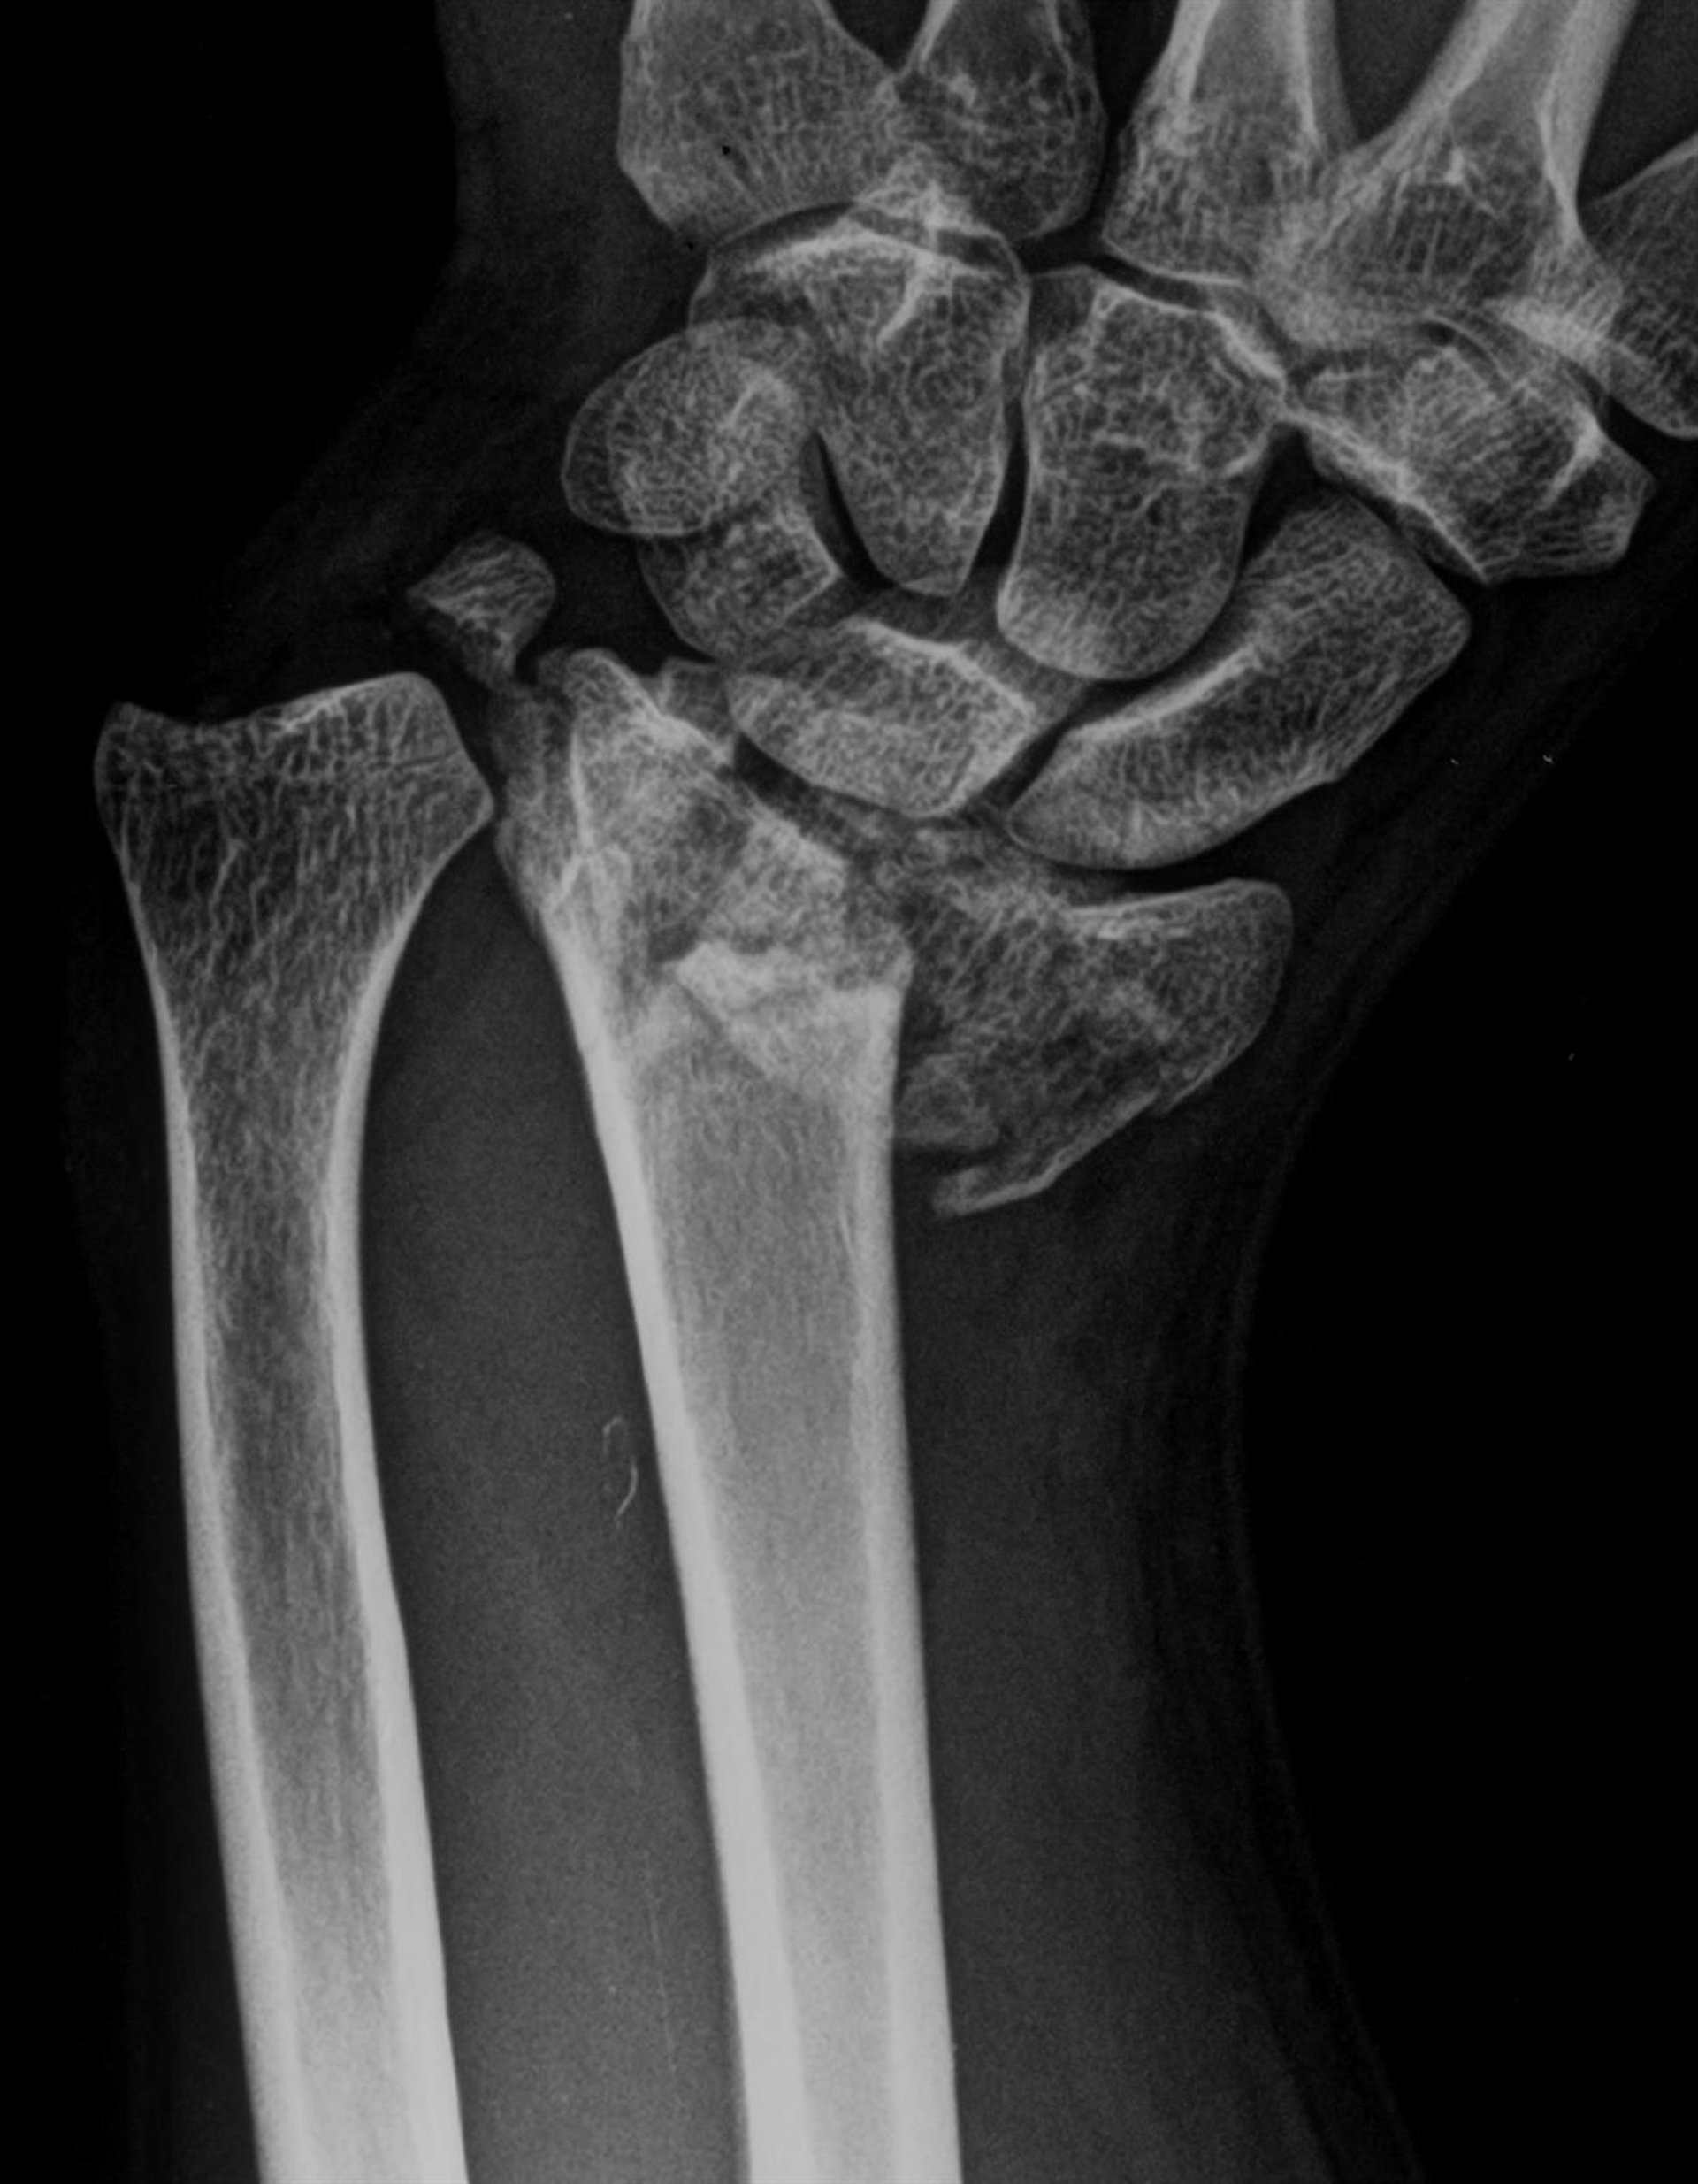

Archivo - Fractura de radio

Archivo - Fractura de radio - HOSPITAL LA LUZ - Archivo

Las fracturas son una patología muy prevalente, siendo las más frecuentes las de cadera (entre 40.000 y 45.000 cada año, según el Registro Nacional de Fracturas de Cadera), muñeca, tobillo y hombro. En cuanto a las principales causas de estas fracturas, destacan las caídas casuales en personas mayores, relacionadas en gran parte con la fragilidad y la osteoporosis y los traumatismos secundarios a accidentes en los más jóvenes (derivados del uso de bicicleta, coche, patinete eléctrico o la práctica de deportes de riesgo).